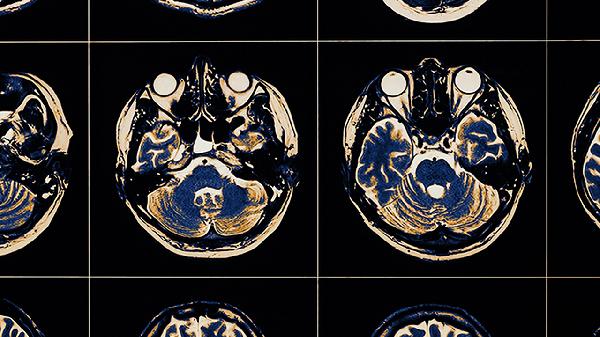

康复期需保证每日蛋白质摄入量达1.2-1.5g/kg体重,优选三文鱼、鸡胸肉等高生物价蛋白。每周3次低冲击有氧运动如游泳、骑自行车有助于维持心肺功能。睡眠时在腘窝处垫薄枕保持膝关节轻度屈曲,可降低晨起僵硬感。损伤后6个月内每月复查韧带张力测试与肌力评估,MRI显示Ⅲ度损伤合并半月板撕裂需考虑关节镜下行韧带重建术。